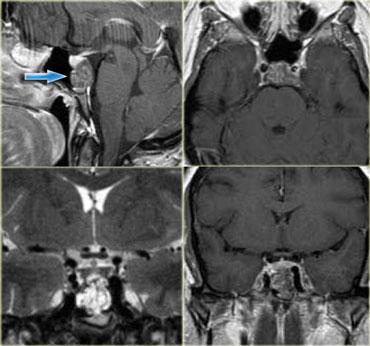

U thần kinh bao (Schwannoma) vùng góc cầu tiểu não với các đặc điểm điển hình của u ngoài trục (Chuỗi xung T2W)

Chuỗi xung T2W cho thấy một u thần kinh bao (schwannoma) nằm ở góc cầu tiểu não (CPA).

Trường hợp này minh họa rõ nét các dấu hiệu điển hình của u ngoài trục.

Có khe dịch não tủy (mũi tên vàng).

Các mạch máu dưới nhện chạy trên bề mặt não bị tổn thương đẩy lệch (mũi tên xanh lam).

Có chất xám nằm giữa tổn thương và chất trắng (mũi tên đỏ cong).

Khoang dưới nhện bị giãn rộng do sự phát triển của tổn thương ngoài trục có xu hướng đẩy lùi não.

Tất cả các dấu hiệu này cho thấy đây là một u ngoài trục điển hình.

Tại vùng góc cầu tiểu não, 90% các u ngoài trục là u thần kinh bao (schwannoma).